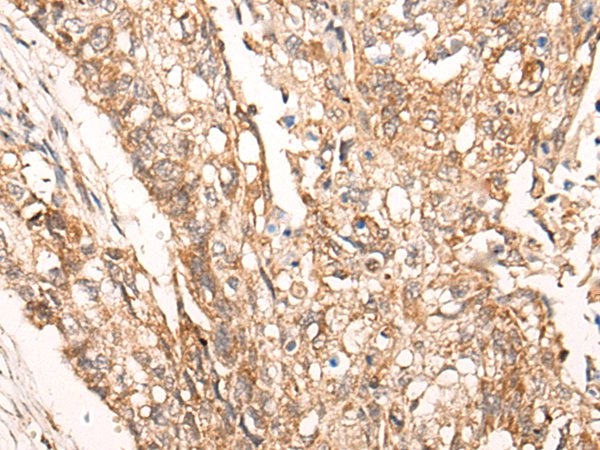

The image is immunohistochemistry of paraffin-embedded Human esophagus cancer tissue using P04640(DGKI Antibody) at dilution 1/25. (Original magnification: ×200) |

The image is immunohistochemistry of paraffin-embedded Human lung cancer tissue using P04640(DGKI Antibody) at dilution 1/25. (Original magnification: ×200) |